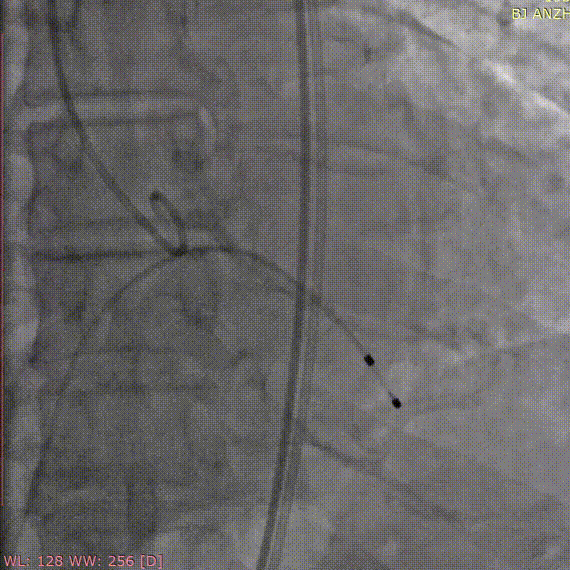

术前造影

定位件入窦

释放瓣膜

术后造影

手术过程和结果

术中采用局部麻醉,经股动脉穿刺建立血管通路,首先采用22mm球囊对病变部位进行预扩张,预扩时无明显腰征及反流,之后将杰成主动脉瓣输送器送入主动脉瓣目标位置,轻松实现定位件的正确入窦,后成功释放22mm瓣膜,之后采用22mm球囊进行后扩张,整个手术过程行云流水,仅用时20分钟。经DSA造影和超声等综合评估显示瓣膜释放位置完美,瓣膜工作稳定,术后即刻主动脉瓣上峰值流速:204cm/s、峰值压力阶差:16mmHg,平均压差:8mmHg,人工主动脉瓣瓣环内无反流,微量瓣周漏,患者临床症状和血流动力学明显改善。